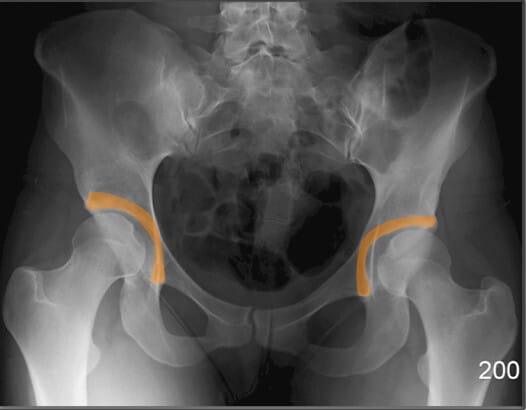

장골능 (Iliac Crest)

| 장골능 (Iliac Crest) |

| ✅ 골반의 가장 상부 경계로, AP pelvis 영상에서 양측 상단에 대칭적으로 보입니다. |

| 🔴 곡선을 이루며, 체위 기준점으로도 활용됩니다. |

전상장골극 (ASIS, Anterior Superior Iliac Spine)

| 전상장골극 (ASIS, Anterior Superior Iliac Spine) |

| ✅ 장골의 앞쪽 윗부분에 돌출된 뼈로, AP view에서 골반의 가장 상전방에 대칭적으로 위치합니다. |

| 🔴 표면해부학에서 중요한 구조로 , 골반의 변위를 대략적으로 파악할 수 있습니다. |